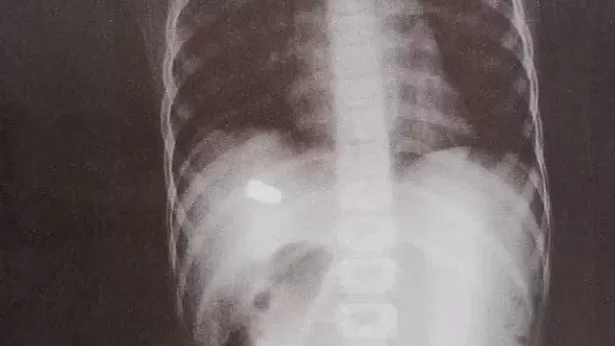

A mulher o levou à Unidade de Pronto Atendimento (UPA) do bairro ao perceber que a criança tinha um sangramento. Na unidade de saúde, onde a criança fez um exame de raio-x, os médicos descobriram que ela tinha sido atingida por um tiro. A Polícia Civil investiga o caso como tentativa de homicídio. A suspeita é de que a criança tenha sido vítima de bala perdida.